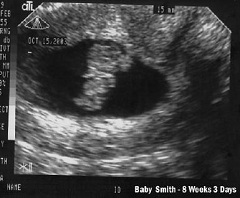

Интенсивно развиваются мышечная, костная и хрящевая ткани, у плода появляется мышечный тонус. Движения будущего малыша ручками и ножками становятся все интенсивнее, их хорошо видно на УЗИ в 8 недель беременности, но будущий младенец еще настолько мал, что мать не ощущает его шевелений. Руки в своем развитии опережают ноги, они крупнее и более дифференцированы – отчетливо можно отличить границы плеча и предплечья, начинают вырисовываться фаланги пальцев, сами пальцы на руках уже отделены друг от друга, перепонки между ними отсутствуют. На стопах же пальчики все еще остаются сросшимися.

Наружные половые органы не сформированы – на месте промежности пока еще находится только бугорок, и по УЗИ в 8 недель беременности невозможно определить пол будущего ребенка.